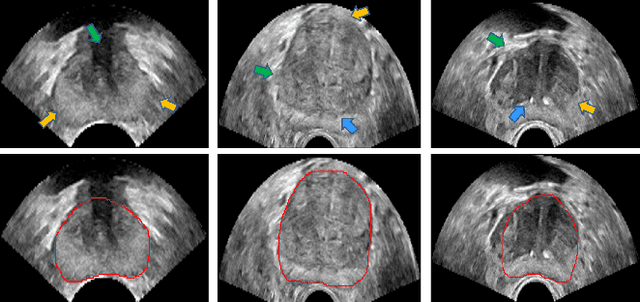

Abstract:Boundary incompleteness raises great challenges to automatic prostate segmentation in ultrasound images. Shape prior can provide strong guidance in estimating the missing boundary, but traditional shape models often suffer from hand-crafted descriptors and local information loss in the fitting procedure. In this paper, we attempt to address those issues with a novel framework. The proposed framework can seamlessly integrate feature extraction and shape prior exploring, and estimate the complete boundary with a sequential manner. Our framework is composed of three key modules. Firstly, we serialize the static 2D prostate ultrasound images into dynamic sequences and then predict prostate shapes by sequentially exploring shape priors. Intuitively, we propose to learn the shape prior with the biologically plausible Recurrent Neural Networks (RNNs). This module is corroborated to be effective in dealing with the boundary incompleteness. Secondly, to alleviate the bias caused by different serialization manners, we propose a multi-view fusion strategy to merge shape predictions obtained from different perspectives. Thirdly, we further implant the RNN core into a multiscale Auto-Context scheme to successively refine the details of the shape prediction map. With extensive validation on challenging prostate ultrasound images, our framework bridges severe boundary incompleteness and achieves the best performance in prostate boundary delineation when compared with several advanced methods. Additionally, our approach is general and can be extended to other medical image segmentation tasks, where boundary incompleteness is one of the main challenges.